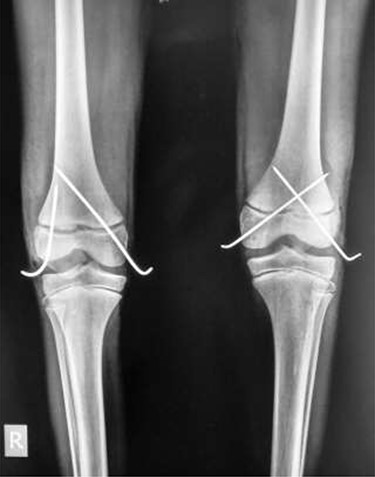

A 9-year-old male presented to the ER within 6 h of injury to both knees, with swelling, restricted movements and tenderness bilaterally. Assessment demonstrated distal pulses in both legs. Initial management was with pain relief—neurological status was not assessed due to pain. A history of direct fall of a concrete block onto both knees whilst sitting with legs extended and raised on a stool at a building site, leading to a forced hyperextension injury, was elicited. The patient received no treatment before presenting to our unit. Radiography suggested bilateral completely displaced Salter-Harris Type I fractures (Fig 1A–C). All routine laboratory and metabolic profiles performed were within normal ranges. Patient was transferred to theatre immediately after radiography for a closed reduction.

(A) Lateral view of right knee at presentation, (B) lateral view of left knee at presentation, (C) frontal view of both knees at presentation